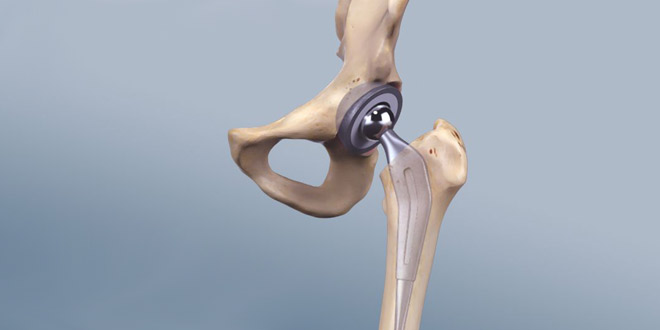

جراحی تعویض مفضل

در جراحی تعویض مفصل لگنمفصل لگن (هیپ) با یک مفصل مصنوعی جایگزین می شود که به این بخش مصنوعی، پروتز گفته می شود. مفصل لگن، از دو بخش اصلی تشکیل شده است؛ که ممکن است در طی عمل جراحی توسط جراح لگن هر دو بخش تعویض شود. این دو بخش شامل حفره لگن، که قسمتی از استخوان لگن به نام استابولوم و انتهای فوقانی استخوان لگن یا سر لگن؛ می باشد.